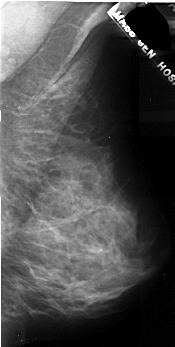

A_1047_1.RIGHT_CC

RIGHT_MLO LINES 5191 PIXELS_PER_LINE 2611 BITS_PER_PIXEL 16 RESOLUTION 42 NON_OVERLAY